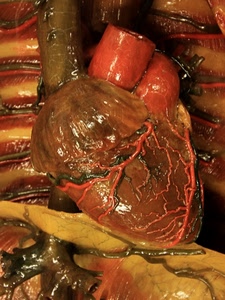

233° Modello di cuore alla Specola

Voto: 27.59 |

234° Modello di cuore umano

Voto: 26.96 |

241° Modello di cuore della Specola

Voto: 16.26 |